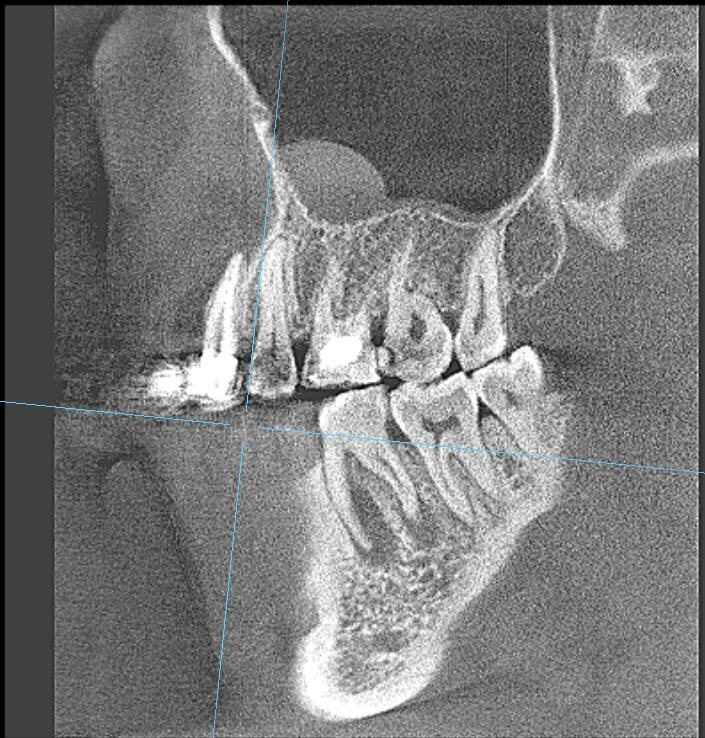

Π― сдСлала ΠšΠ›ΠšΠ’. ЧСстно скаТу Π½Π°Π΄Π΅ΠΆΠ΄Ρ‹ Π±Ρ‹Π»ΠΎ ΠΌΠ°Π»ΠΎ...ΠžΡ‡Π°Π³ воспалСния впСчатлял ΠΌΠ°ΡΡˆΡ‚Π°Π±Π°ΠΌΠΈ. Π― прямо сказала ΠœΠ°Ρ€ΠΈΠΈ: ΡˆΠ°Π½ΡΡ‹ Ρƒ Ρ‚Π°ΠΊΠΎΠ³ΠΎ Π·ΡƒΠ±Π° 50 Π½Π° 50, Π½ΠΎ ΠΏΠΎΠΏΡ€ΠΎΠ±ΠΎΠ²Π°Ρ‚ΡŒ ΠΌΠΎΠΆΠ½ΠΎ πŸ€”

ΠŸΡ€ΠΎΡˆΡ‘Π» Ρ†Π΅Π»Ρ‹ΠΉ Π³ΠΎΠ΄...И Π²ΠΎΡ‚ ΠΎΠ½Π° снова Π² ΠΌΠΎΡ‘ΠΌ расписании. Π”Π΅Π»Π°Π΅ΠΌ ΠΊΠΎΠ½Ρ‚Ρ€ΠΎΠ»ΡŒΠ½ΡƒΡŽ ΠšΠ›ΠšΠ’ ΠΈ видим… ΠΏΠΎΠ»Π½ΠΎΠ΅ Π·Π°ΠΆΠΈΠ²Π»Π΅Π½ΠΈΠ΅ ΠΎΡ‡Π°Π³Π°!Ни слСда воспалСния!